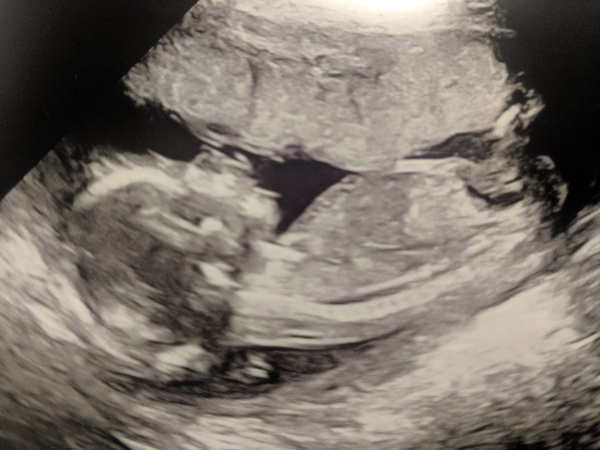

20 week scan yesterday, baby is all good. We didn’t find out the sex but both think it’s another girl and we didn’t see anything obvious! So cute, baby had their hands up on each side of their face, we saw really clear images of the face, lips, feet. Forgot the detail (and how long it is) you see at that scan x